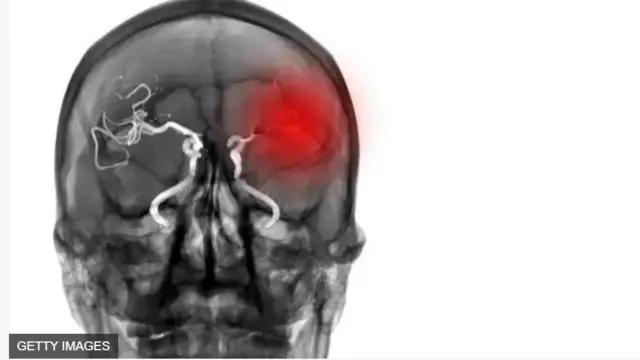

Oríṣun àwòrán, Getty Images

Gẹgẹ bi Dokita Kwalifa ṣe ṣalaye, rọparọsẹ maa n waye nigba ti ẹjẹ ba dì, ti opo to n gbe ẹjẹ lọ sinu ọpọlọ ko ba le gbe ẹjẹ lọ sibẹ mọ, tabi ti opo ẹjẹ ba bẹ, ti ẹjẹ ko raye denu ọpọlọ mọ.

Ọna meji ni rọparọsẹ pin si, bi Dokita Kwalifa ṣe ṣalaye.

Akọkọ ni rọparọsẹ to waye latari aito ẹjẹ to n lọ sinu ọkan.

Ikeji ni eyi to ṣẹlẹ latari ẹjẹ to di to si tuka sinu ọpọlọ tabi si itosi rẹ.